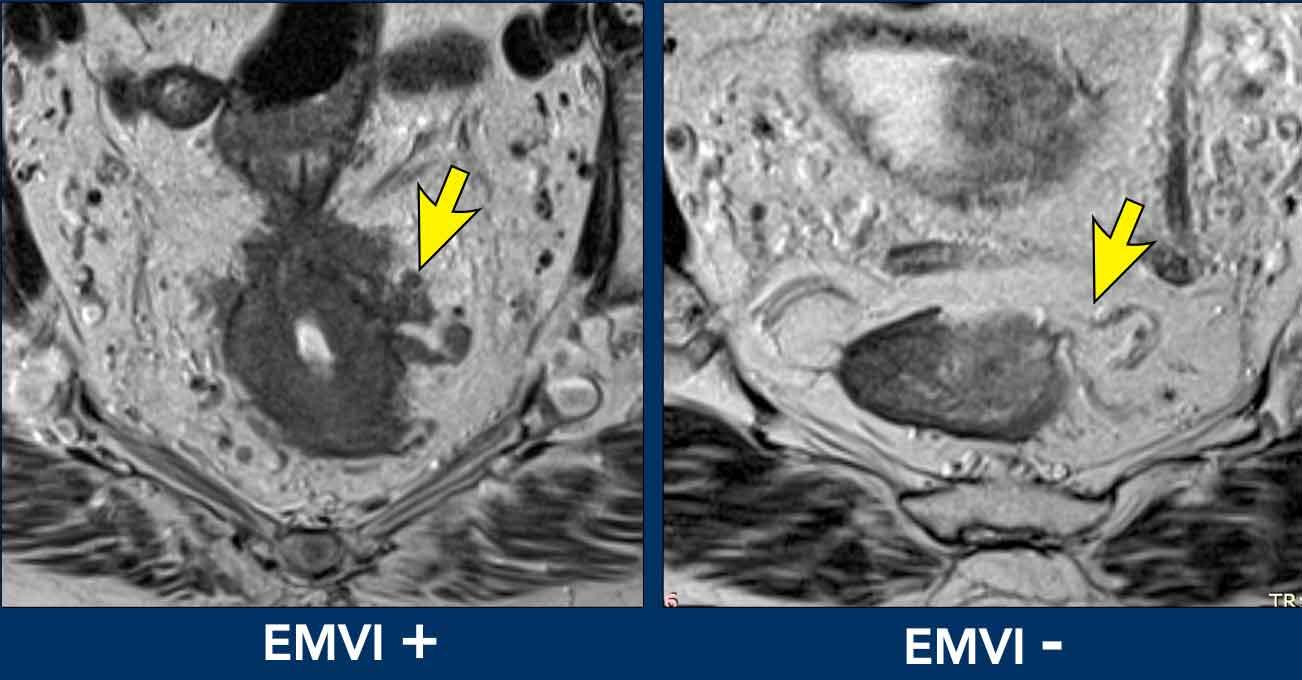

Cạm bẫy: đánh giá quá mức xâm lấn mạch máu ngoài thành ruột (EMVI)

Các mạch máu quanh trực tràng bình thường có đường kính khác nhau thường tỏa ra từ lớp cơ thành ngoài vào trong mỡ mạc treo trực tràng.

Đừng nhầm lẫn những hình ảnh này với EMVI trừ khi có bằng chứng rõ ràng về xâm lấn khối u—được định nghĩa là tín hiệu khối u lan vào, làm giãn rộng hoặc phá vỡ đường viền của mạch máu.

Mẹo Đánh Giá Quan Trọng

Đánh giá vị trí theo chu vi của khối u trong thành trực tràng.

Các mạch máu không xuất phát từ vị trí bám dính của khối u không bao giờ được phân loại là EMVI, bất kể mức độ nổi bật như thế nào.

So sánh hình ảnh

- Trái (EMVI+):Tín hiệu khối u rõ ràng lan vào các mạch máu lân cận, làm gián đoạn đường viền của chúng.

- Phải (EMVI-):Các mạch máu duy trì đường viền trơn nhẵn và không có tín hiệu khối u.